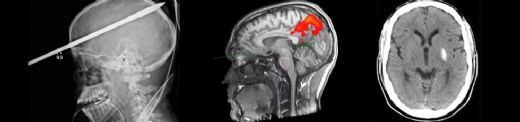

Çocuklarda beyin kanaması, çeşitli nedenlerle meydana gelebilen ciddi bir sağlık sorunudur. Bu durum, çocukların beyin dokusunun zarar görmesine ve yaşamı tehdit eden komplikasyonların ortaya çıkmasına yol açabilir. Beyin kanaması, kafatası içindeki kan damarlarının yırtılması veya sızdırması sonucu meydana gelir ve belirtileri, kanamanın türüne, yerine ve şiddetine bağlı olarak değişiklik gösterir. Beyin Kanaması Türleri Beyin kanamaları, çeşitli tiplere ayrılmaktadır. Bu türler arasında en yaygın olanları şunlardır:

Her bir kanama türü, farklı nedenlere, belirtilere ve tedavi yöntemlerine sahiptir. Belirtiler Çocuklarda beyin kanaması belirtileri, durumun ciddiyetine göre değişiklik gösterebilir. Aşağıdaki belirti ve semptomlar, beyin kanaması yaşayan bir çocukta gözlemlenebilir: